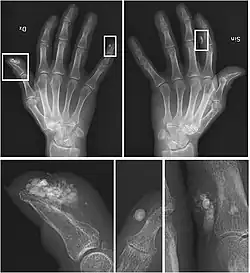

Se debe realizar una historia clínica detallada y solicitar una analítica general que incluya función renal, sodio, potasio, calcio corregido, fósforo y el producto de ambos, amilasa, lipasa, creatina cinasa (CK), aldolasa, paratohormona (PTH), enzima convertidora de angiotesina (ECA), vitamina D, autoinmunidad, hemograma, gasometría (bicarbonato, pH), orina de 24 horas con excreción de calcio y fósforo.

También se deben hacer pruebas de imagen como radiografías y TAC (tomografía axial computarizada) en las que se puedan objetivar las calcificaciones.